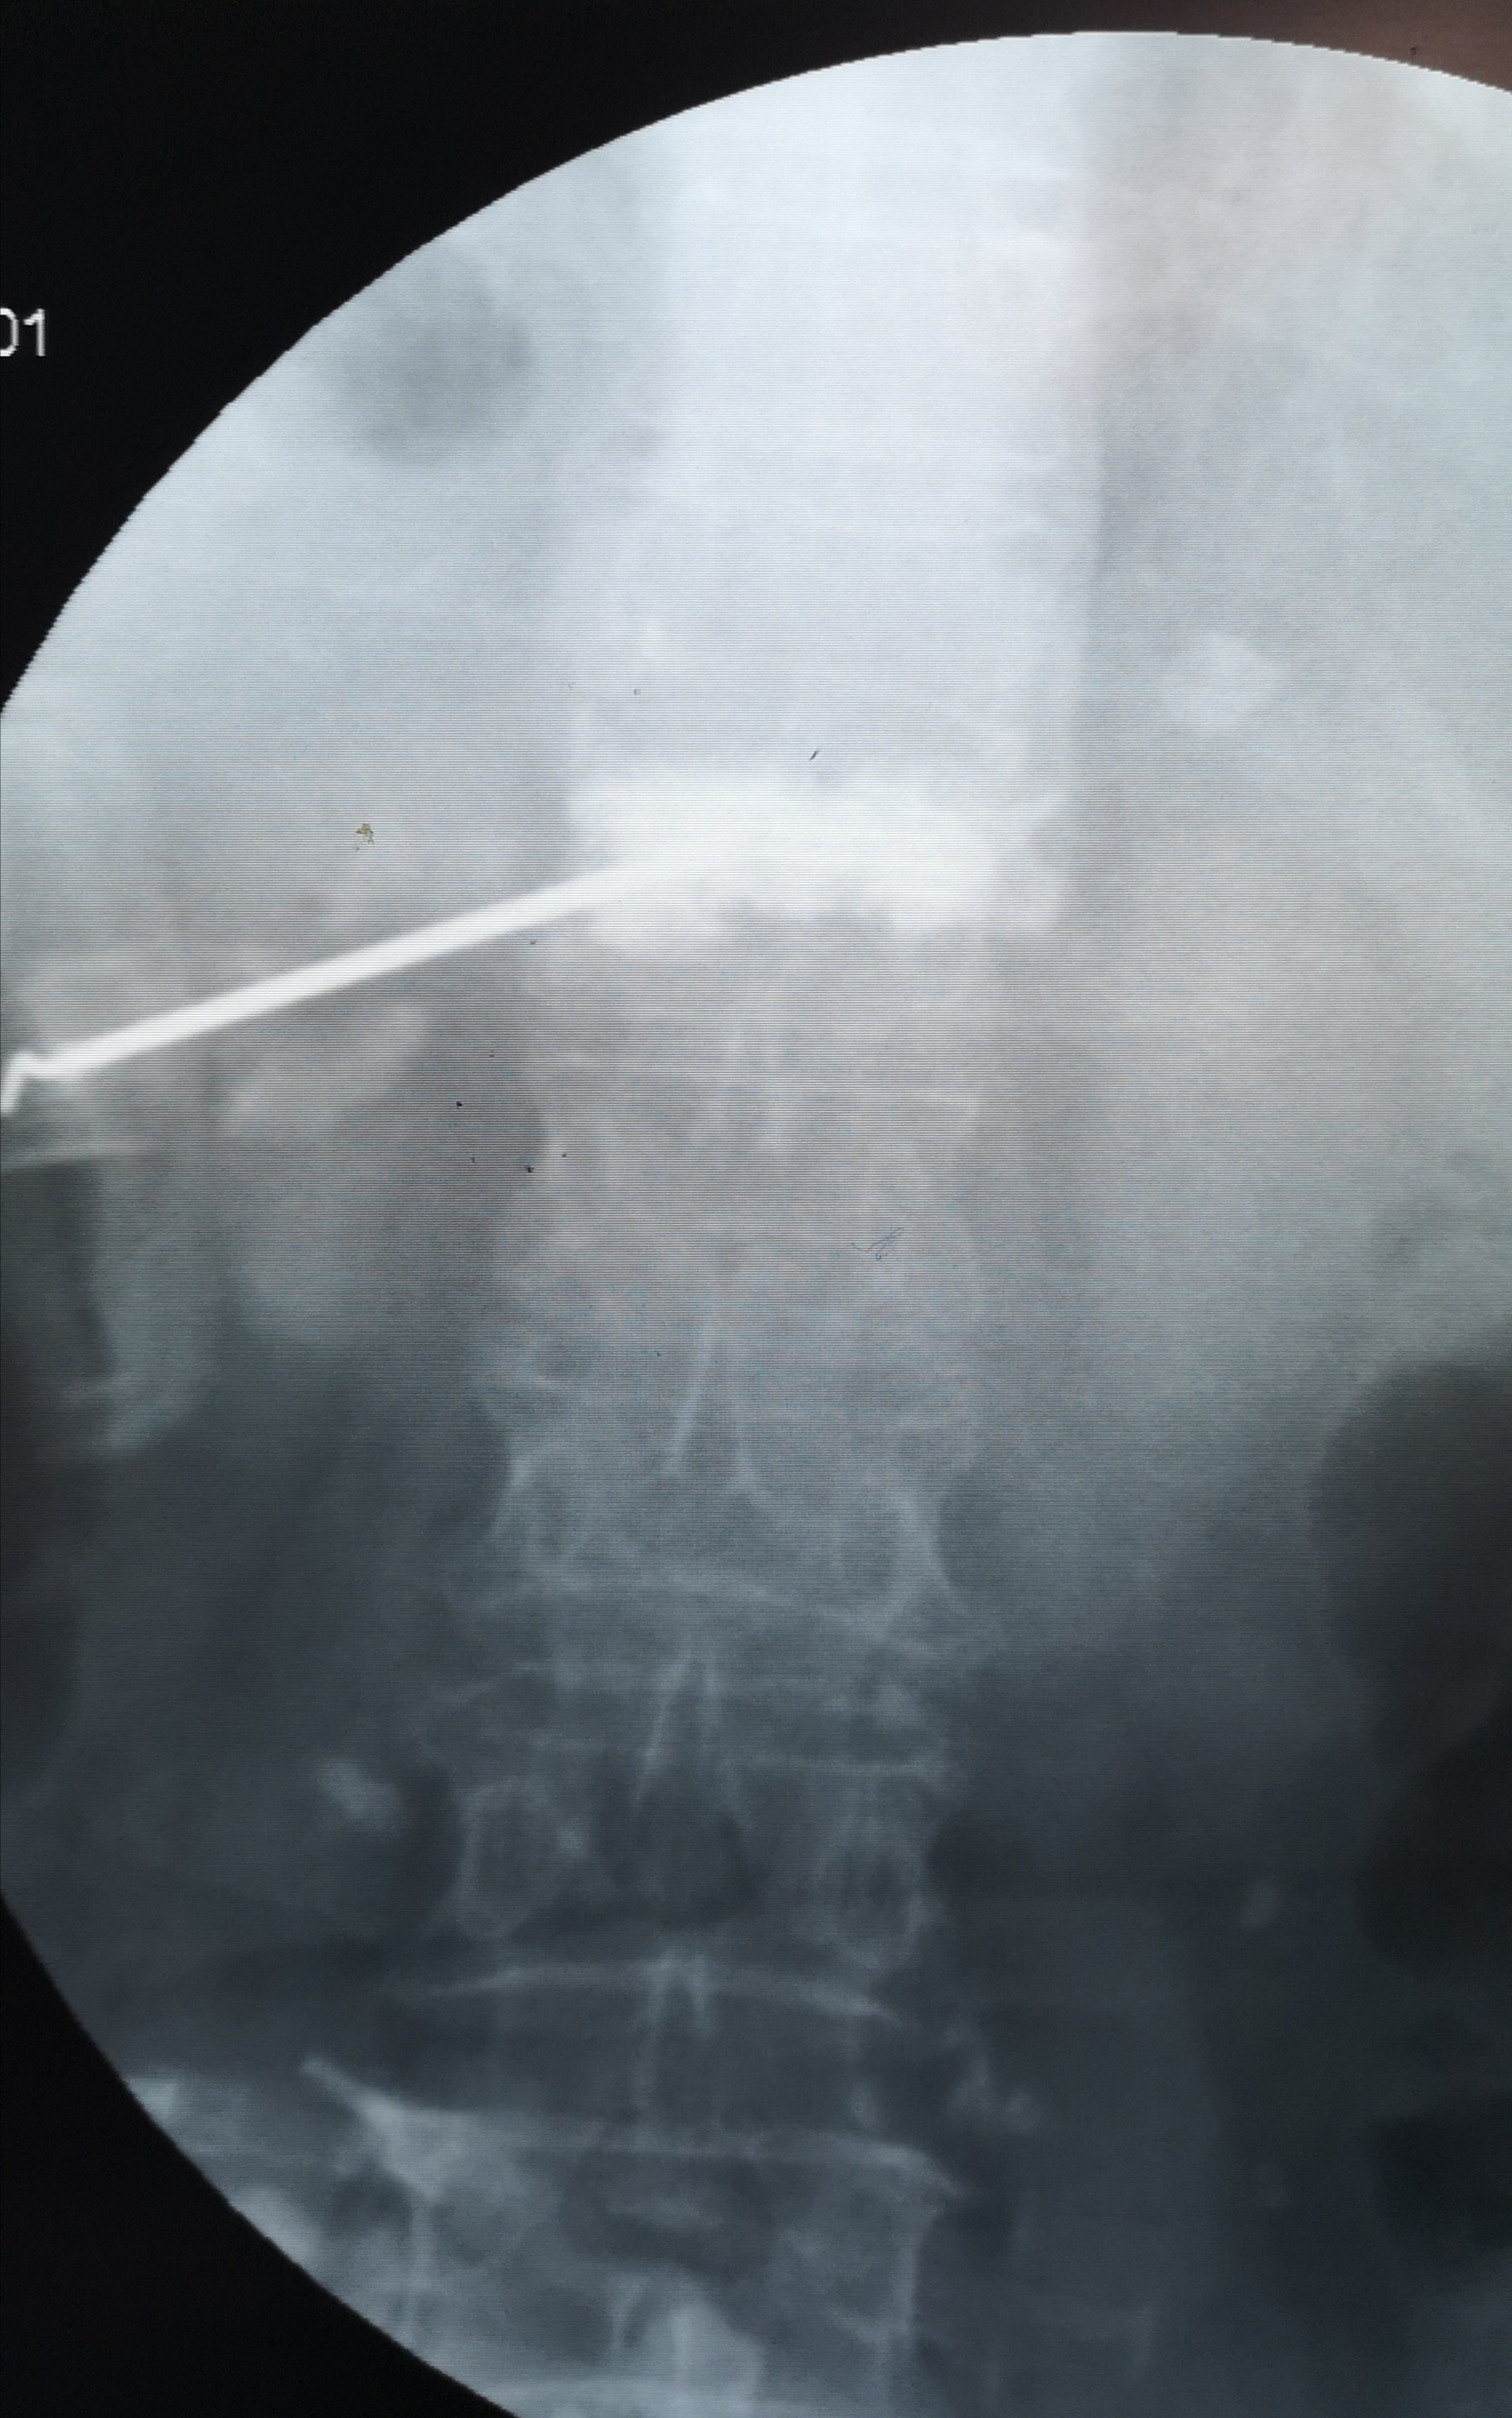

腰2椎体压缩性骨折,闭合复位微创经皮钉棒系统内固定手术治疗.